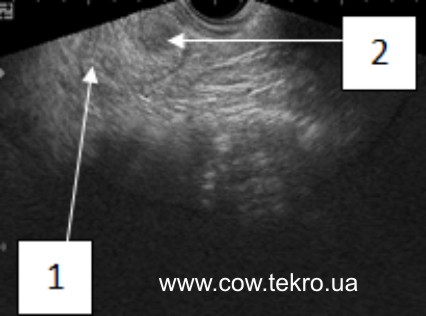

За ультразвукового дослідження структура тканин жовтого тіла неоднорідна, дрібнозерниста. Від тканин яєчника відрізняється зниження ехощільності (має темно-сіре зображення) (рис. 6).

Рисунок 6 –Ехограма яєчника корови з персистентним жовтим тілом: 1 – тканини яєчника; 2 – жовте тіло